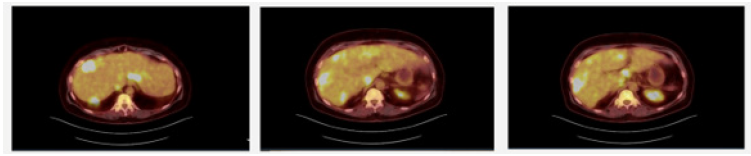

We present a 53-year-old female with diffuse hepatic lesions and widespread lymphadenopathy who was referred to Hepato- pancreato-biliary clinic for evaluation after several failed and inconclusive needle biopsies. She originally presented to her primary care physician for evaluation due to a 4-month history of fevers, chills, drenching night sweats, fatigue, postprandial pain and 40-pound weight loss. Routine labs were unremarkable besides thrombocytosis. CT abdomen and pelvis demonstrated porta hepatis lymphadenopathy and multiple liver lesions (Figure 1). On PET scan she was found to have innumerable masses in the liver and axillary, mediastinal, porta hepatis and retroperitoneal lymphadenopathy with FDG uptake concerning metastatic disease (Figure 2). She was sent to interventional radiology for CT-guided biopsy which revealed necrotizing granulomatous inflammation. Auramine-protamine and AFB staining were negative. She was referred to infectious disease, but extensive workup was negative. Repeat IR biopsy showed fibroinflammatory cells with chronic lymphoplasmacytic and histiocytic inflammation. Given numerous inconclusive results with percutaneous biopsies she was referred to surgery clinic by infectious disease for excisional biopsy. Given her concerning symptoms, lymphoma was also a consideration making surgery a reasonable approach for excisional biopsy with lymphoma protocol. She was seen and evaluated in clinic where we discussed laparoscopic vs an open approach and she elected to undergo an open biopsy. Intraoperatively she was found to have innumerable liver lesions and diffuse porta hepatis lymphadenopathy. Multiple excisional biopsies were obtained from hepatic segments 4, 5, and 6. These were sent for frozen section and permanent. Some of the lesions were sent for microbiology and others sent for cultures, including TB, fungal, anaerobic and aerobic. The hilar lymph nodes were sent for per lymphoma protocol. The frozen section came back as chronic inflammation, non-diagnostic. Permanent biopsies all revealed necrotizing granulomatous inflammation. Cultures were negative for infectious organisms.